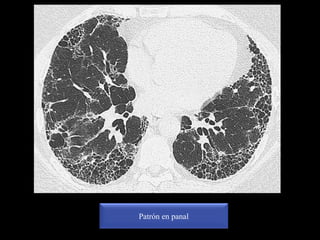

*Quistes de diferentes tamaños de paredes gruesas bien

definidas dispuestos en diferentes capas

*Típicamente los quistes comparten pared con los quistes

adyacentes

*La localización más frecuente es en regiones periféricas y

subpleurales

*Con frecuencia asociado a otros signos de fibrosis pulmonar:

Distorsión de la arquitectura, engrosamiento intersticial intralobulillar,

bronquiectasias o bronquioloectasias de tracción, engrosamiento subpleural

irregular, densidades lineales irregulares

PATRÓN EN

PANAL

Distribuido

predominantemente

subpleural, posterior y en

lúbulo inferior

NIU (FPI)

Patrón en panal